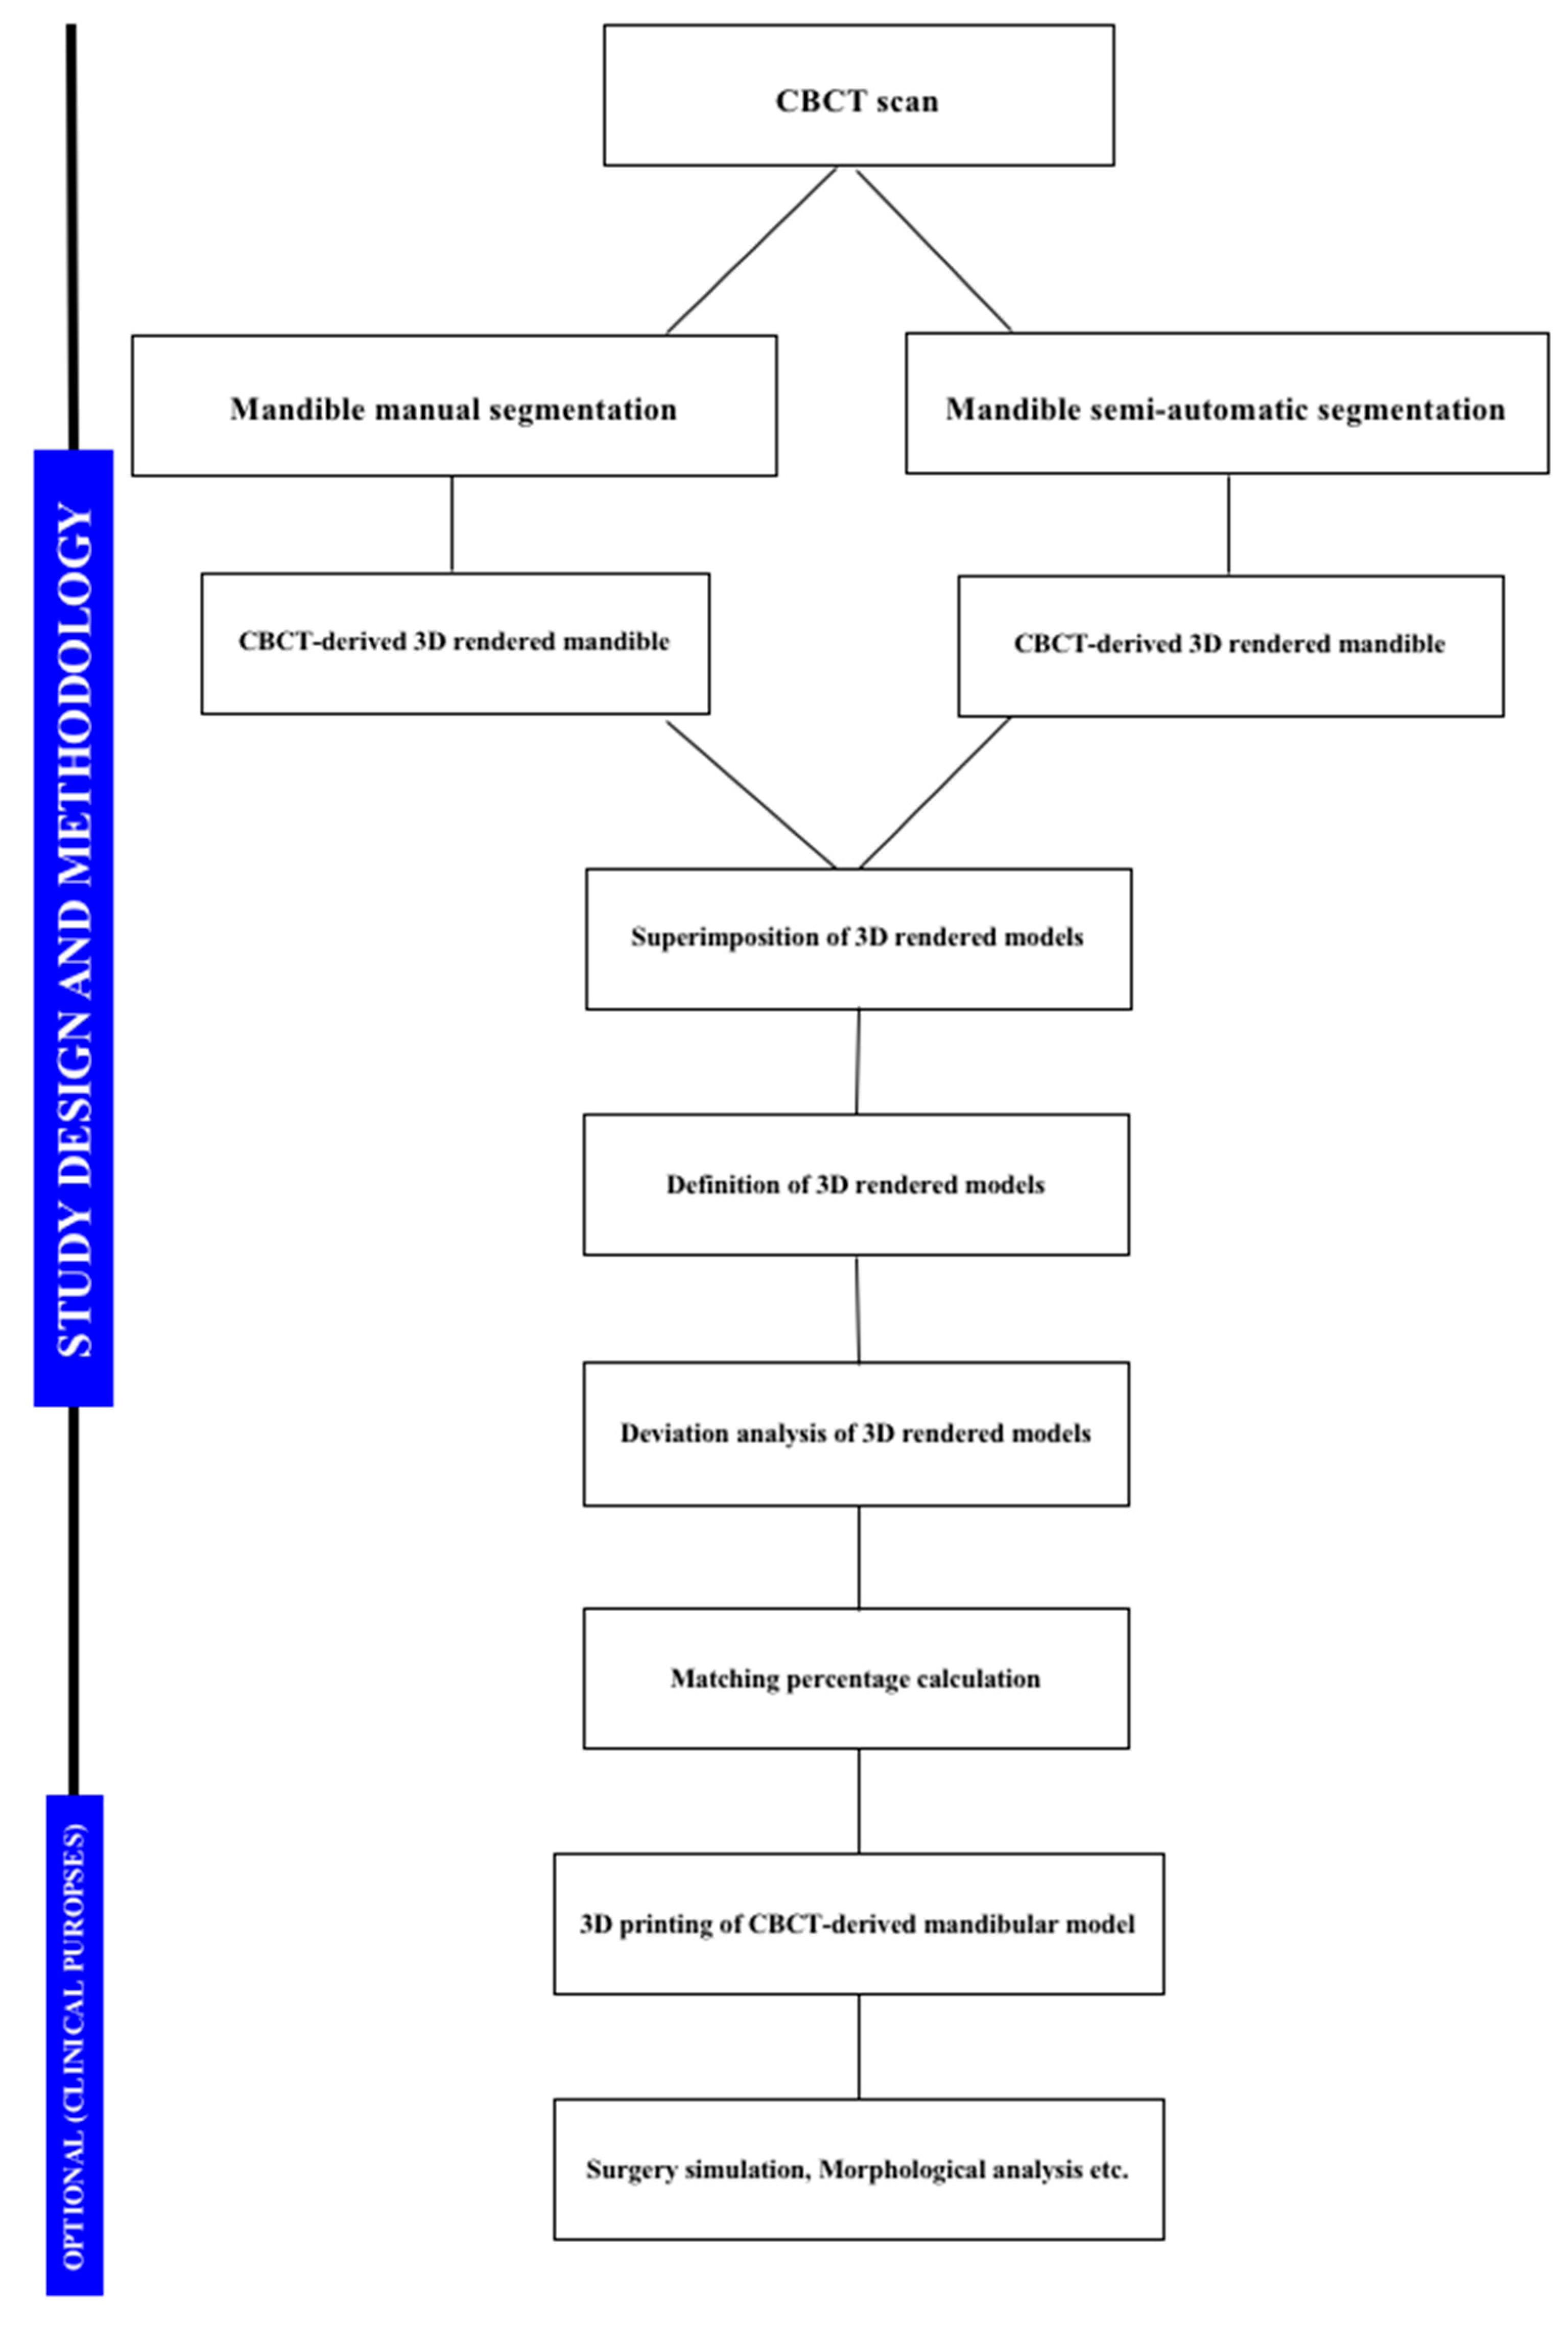

2. Materials and Methods